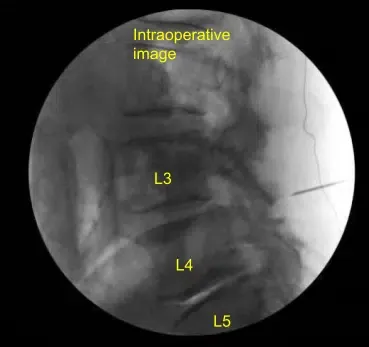

Se utilizó la aguja espinal para localizar el nivel L4-L5 en el lado derecho. Se demarcó una incisión lineal de 1,8 cm que se infiltró con anestesia local. La piel se abría con un bisturí de 10 cuchillas. Se obtuvo hemostasia con Bovie y se utilizó Bovie para dividir bruscamente la fascia. Se usaban dilatadores secuenciales para acoplar un separador tubular de 18 mm x 5 cm que se fijaba rígidamente al marco de la cama.